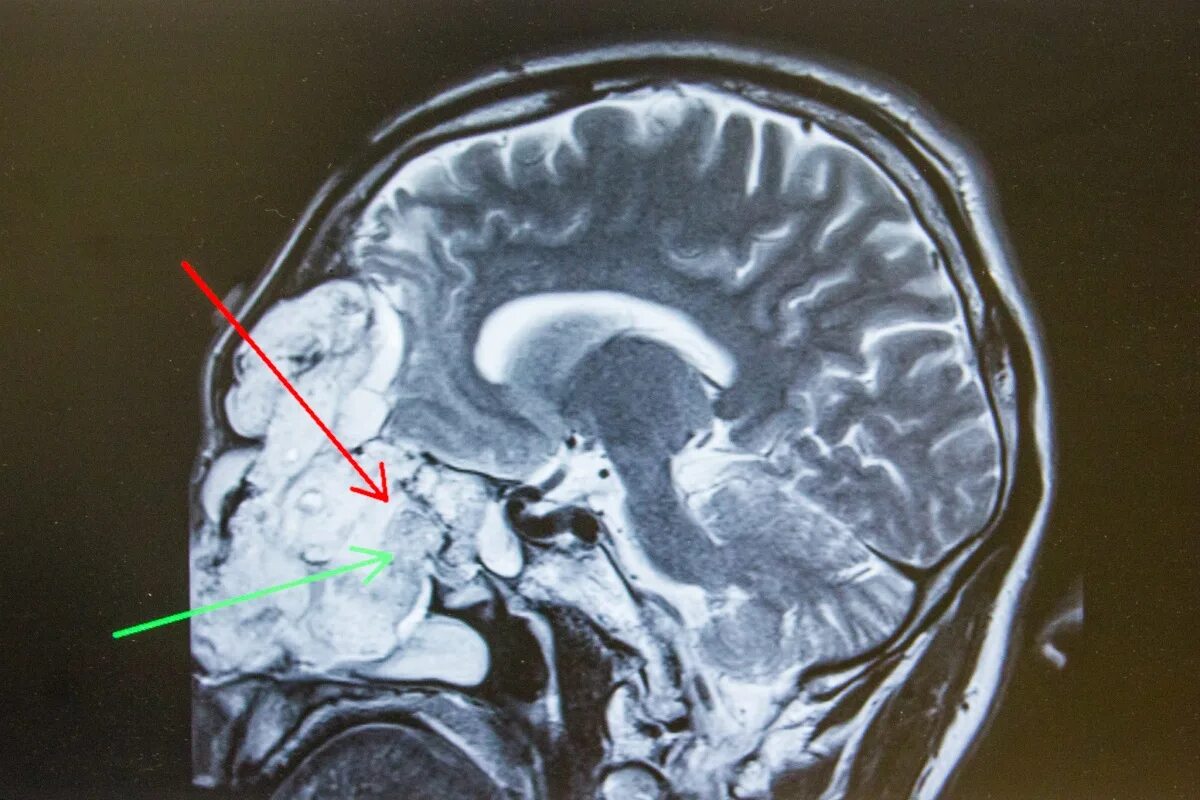

Какие опухоли в голове